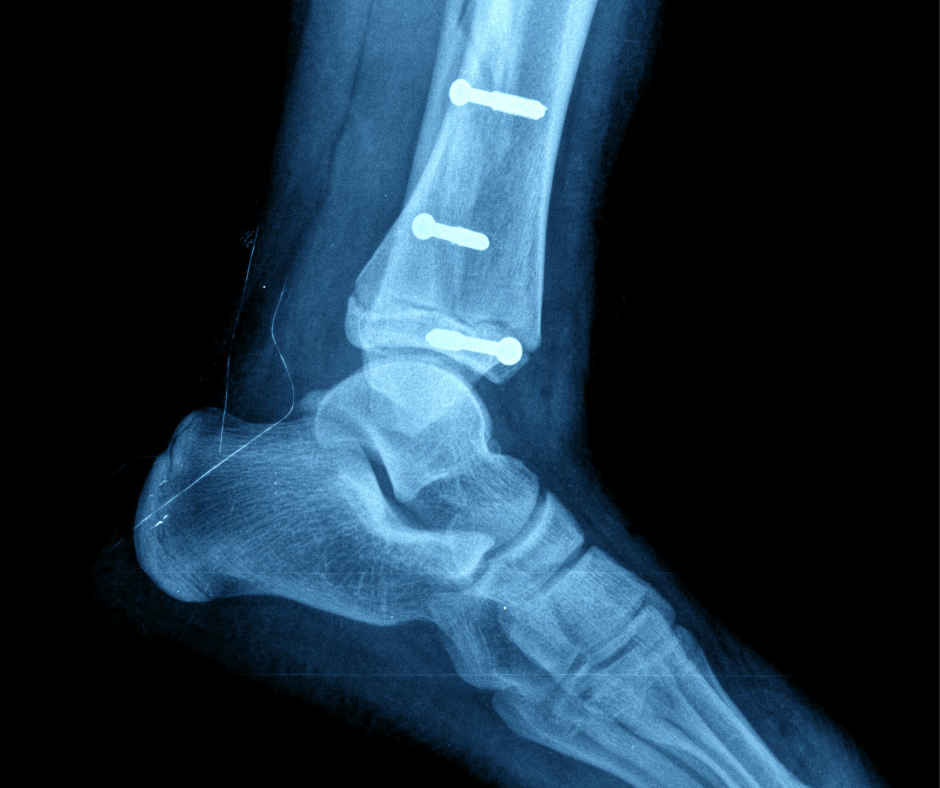

Understanding Foot Recovery with Surgical Screws

In foot treatment, surgical screws are essential for stabilizing fractures and assisting the healing process. To maintain correct alignment and speed recovery, these operations entail inserting specialized screws into the foot’s bones. Let’s discuss what we treat and the importance…

Threaded Healing: The Intricate Role Of Surgical Screws In Foot

In foot treatment, surgical screws are essential for stabilizing fractures and assisting the healing process. To maintain correct alignment and speed recovery, these operations entail inserting specialized screws into the foot’s bones. Let’s discuss ,what we treat and the importance…

Foot Makeover Chronicles: Hammer Toe Surgery With Screws

If you’re suffering from a hammer toe deformity, the thought of having to undergo surgery might be daunting. However, advances in medical techniques have made it possible to treat this condition safely and effectively using surgical screws. n The team…